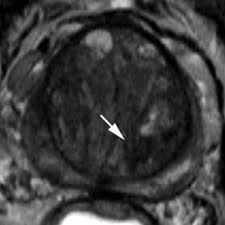

Transitional Zone Prostate Cancer Mri - Multi Parametric Mr Imaging Of Transition Zone Prostate Cancer Imaging Features Detection And Staging / Here are 10 more facts about prostate cancer.

Transitional Zone Prostate Cancer Mri - Multi Parametric Mr Imaging Of Transition Zone Prostate Cancer Imaging Features Detection And Staging / Here are 10 more facts about prostate cancer.. It sits directly beneath your bladder and in front of your rectum. Or, you can choose another section to learn more about a specific question you have. But hearing the words can still be scary. The earlier the detection of prostate cancer, the better the patient's chance of survival is. Find the information you need today.